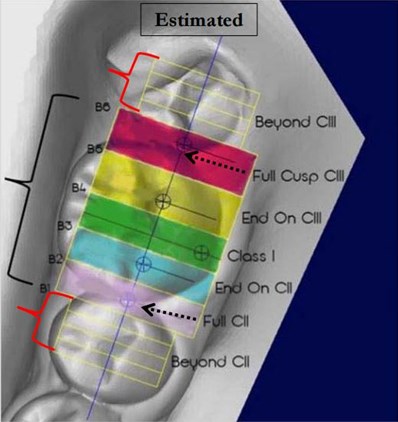

Illustration #1 of 3: Full-Step Class II Molar Relationship

For the malocclusion to satisfy the ABO definition of a full-step Class II molar relationship, the mesiobuccal cusp of the maxillary permanent first molar must occlude, at least on one side, in the embrasure between the mandibular second premolar and the mandibular permanent first molar, or farther to the mesial. If the maxillary or mandibular permanent first molar is missing, the buccal cusp of the maxillary second premolar must occlude in the embrasure between the mandibular first and second premolars, or farther to the mesial. If the maxillary permanent first molar has drifted mesially due to premature loss of the deciduous second molar, that is not considered a full-step Class II molar relationship.